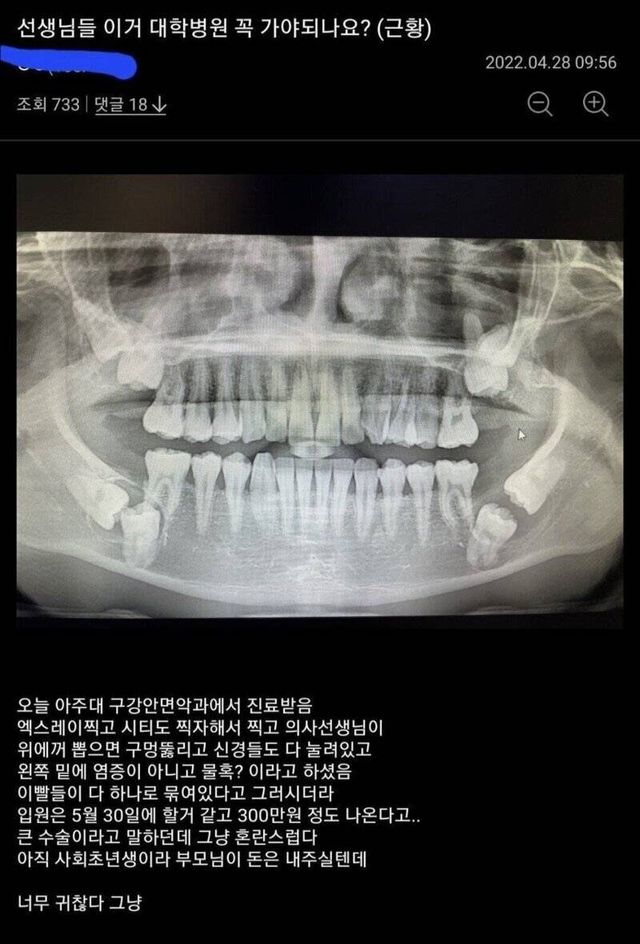

레전ㄷ 사랑니 근황